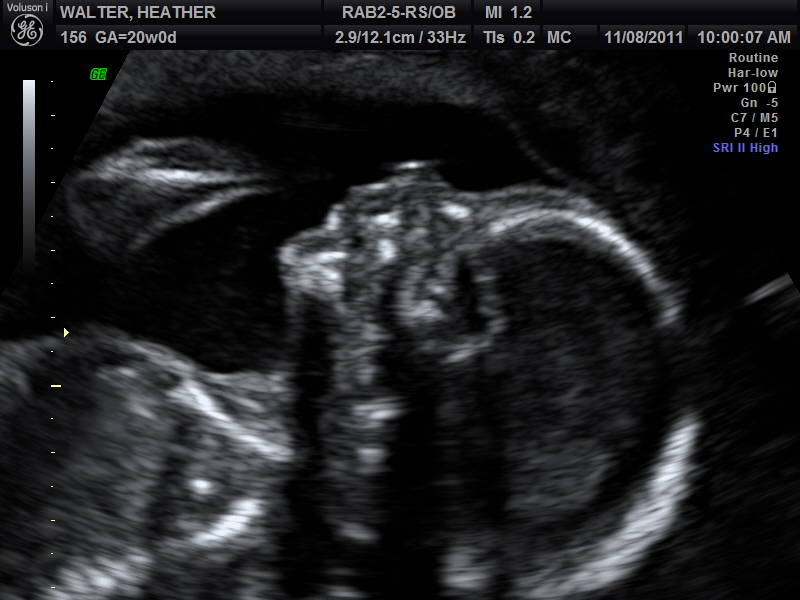

Here are a few of the pictures from the sonogram itself:

Profile with her hand up near her face: